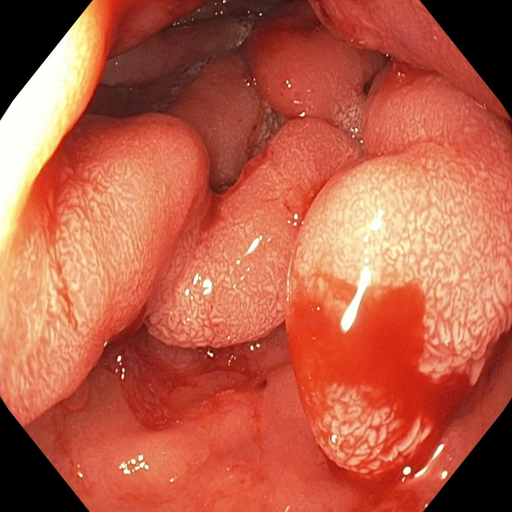

Automated gastrointestinal polyp segmentation presents significant challenges due to various factors illustrated in Fig. 1(b). Uneven illumination from body fluid reflection can degrade image quality, while noise artifacts like surgical instruments and intestinal contents complicate segmentation. Low contrast between tissues hinders accurate polyp localization and identification. Additionally, residual stool and digestive fluids can obscure internal tissues, making differentiation difficult. Polyp boundaries are blurred or unclear due to similar appearance patterns. Furthermore, inter-patient variability and diverse polyp types exhibit various colors and textures. Moreover, an imbalance in pixel distribution, as shown in Fig. 1(c), with the background area often exceeding the polyp area, introduces noise that affects segmentation performance.

Fig. 7 offers qualitative validation, showcasing MNet-SAt’s superior polyp mask generation compared to baselines across four cases. This qualitative superiority aligns with the previously established quantitative results. In the case of small polyps (first and fifth rows), all baseline methods initially appear to produce satisfactory visual results. However, upon closer inspection, they fail to maintain fine boundary details. Our framework excels in preserving polyp anatomy and topology for medium and large polyps, significantly outperforming the baseline methods. Notably, even in multiple polyps, our framework successfully captures more polyps and approximates the ground truth more closely. The primary reason for this superior performance is the EGFE module, which effectively eliminates noise in conjunction with the HMAtt module, resulting in a few false positives. Our analysis reinforces MNet-SAt’s effectiveness in handling challenging polyp scenarios (small, medium, large-scale, and multi-polyps) while suppressing non-regions of interest.